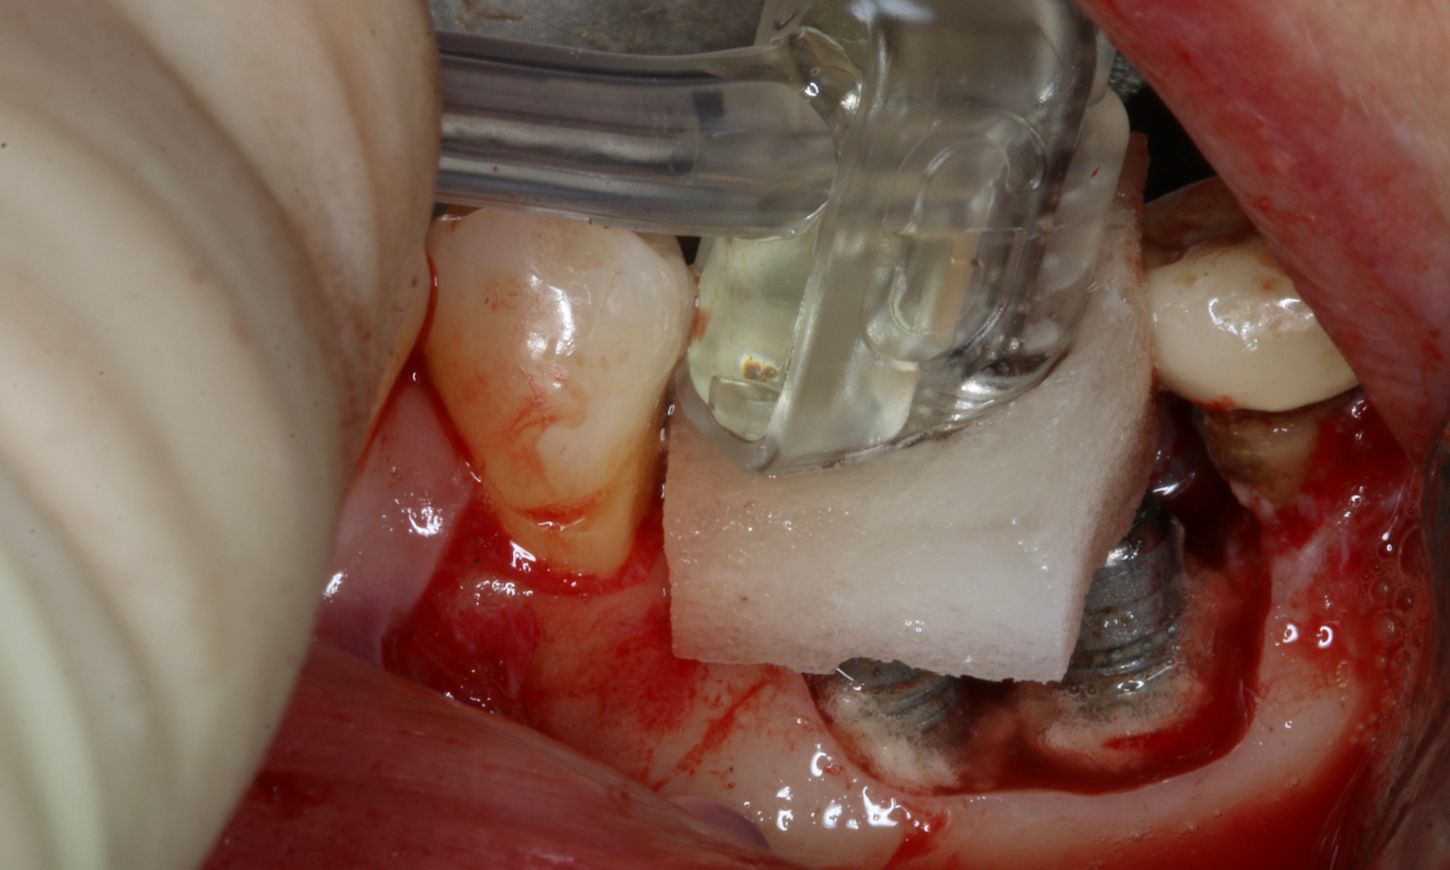

After the non-surgical treatment, clinical examination in 2021 showed a decrease in inflammation, though it was not completely resolved (Fig. 2). Lidocaine 2% with epinephrine 1:100,000 was administered. Upon removal of the prosthesis, the peri-implant mucosa surrounding the implants in positions #36 and #37 exhibited localized inflammation with evident redness, swelling and bleeding (Fig. 3).

Fig. 3

A full-thickness flap was elevated to access the defect and mechanically remove the granulation tissue surrounding the implants (Fig. 4). The bone defect was assessed using the modified criteria established by Monje et al, and was classified as a Class 3b defect, making it suitable for reconstructive therapy. First, implant disinfection was done with ablative mechanical debridement, CHX 0.12 %, metronidazole 5mg/ml, and a solution of local antibiotic and hyaluronic acid (Fig. 5).